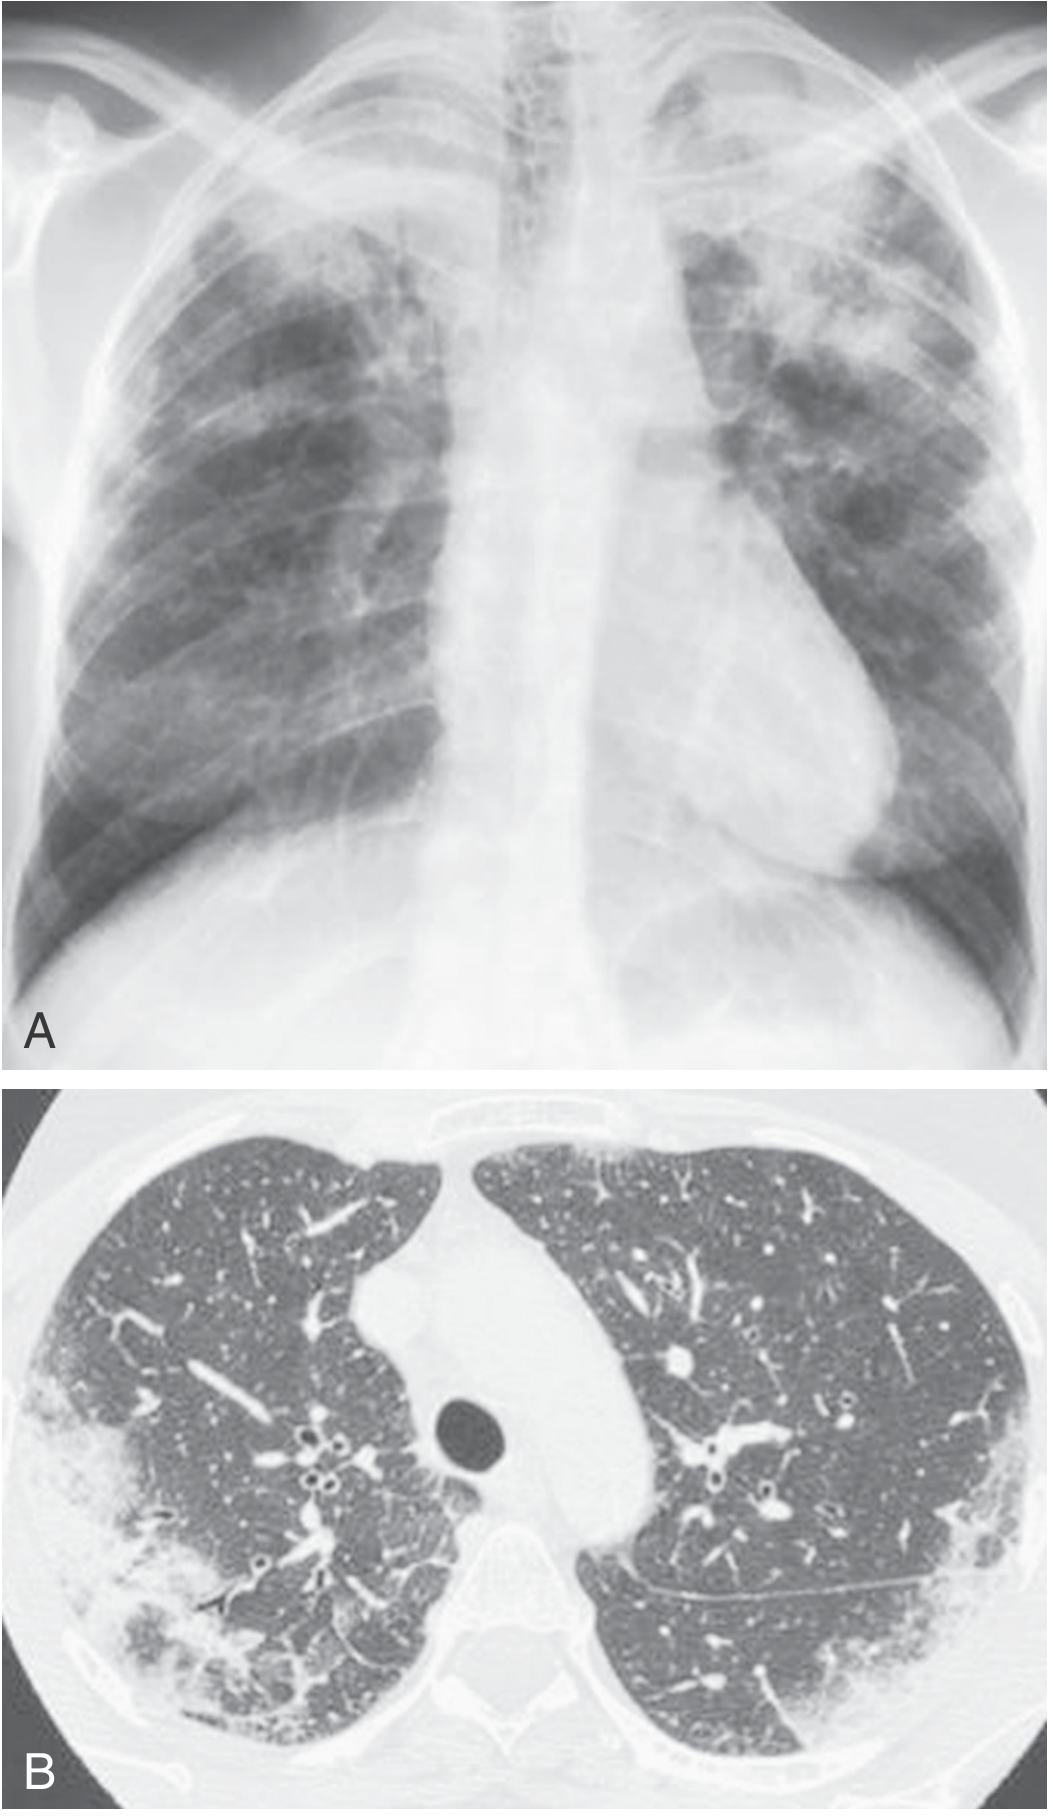

CXR showing bilateral upper-lobe alveolar opacities (A) and axial HRCT showing bilateral symmetrical peripheral opacities (B) in ICEP

Fig: CXR (A) bilateral upper-lobe opacities; HRCT (B) symmetrical peripheral opacities in ICEP (Murray & Nadel's)

Chest Radiograph

• Peripheral, patchy, non-segmental areas of consolidation, predominantly in mid and upper lung zones

• The classic "photographic negative of pulmonary edema" (Gaensler & Carrington sign): dense peripheral opacities paralleling the chest wall, with a clear central zone — seen in only 25–50% of cases

• Infiltrates are typically bilateral, non-segmental, subsegmental, or lobar

• May be migratory in up to 25% of cases

• Pleural effusions and cavitation are rare